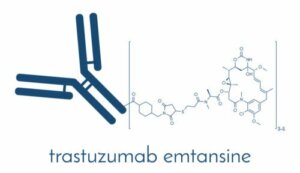

Lek ten to humanizowane przeciwciało monoklonalne, czyli substancja zawierająca przeciwciała produkowane przez limfocyty B należące do układu odpornościowego.

Jest to zatem kombinacja przeciwciał ludzkich z niewielką porcja przeciwciał monoklonalnych szczurów. Część zwierzęcego przeciwciała dołącza się do antygenu, a ludzka część zmniejsza prawdopodobieństwo zniszczenia go przez organizm.

Trastuzumab działa na receptory HER-2 w komórkach piersi uniemożliwiając namnażanie się komórek z nadekspresją tego receptora, a w konsekwencji powoduje ich śmierć. Wywołuje także odpowiedź immunologiczną przeciwko komórkom z nadekspresją receptora HER-2.